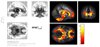

Figure 4

Voxel-wise comparison: linear and non-linear relationship between FA and age. Fractional anisotropy demonstrated a significantly greater non-linear relationship with age compared to a linear relationship, primarily in posterior brain regions such as the splenium of the corpus callosum, large bilateral regions of occipital white matter, bilateral cerebellar white matter, right inferior fronto-occipital fasciculus, and right posterior corona radiata. Small anterior regions also showed a significant difference between the two slopes, including left anterior thalamic radiation, left superior corona radiata, and the right anterior limb of the internal capsule. Colors are representative of a T-score, shown by the color bar in the top left